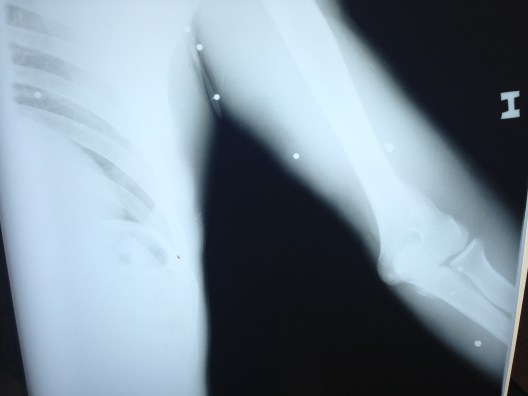

Shotgun pellet wounds, in the pelvis

more pellets

The nurses called me today to attend to a young man who had been shot twice. (and this time I understood what she said, whoohoo!) Actually, he had 38 projectiles in his body that I could count, despite only being shot twice. The assailants had used a shotgun. Luckily, they were far enough away that the pellets had dispersed and didn’t penetrate deep enough to puncture lung, significant blood vessels, or bone. This poor fellow tells me it was done by one of the gangs (Maras), who were trying to steal his ‘work’. He made his way 4 hours to come to our hospital for care.